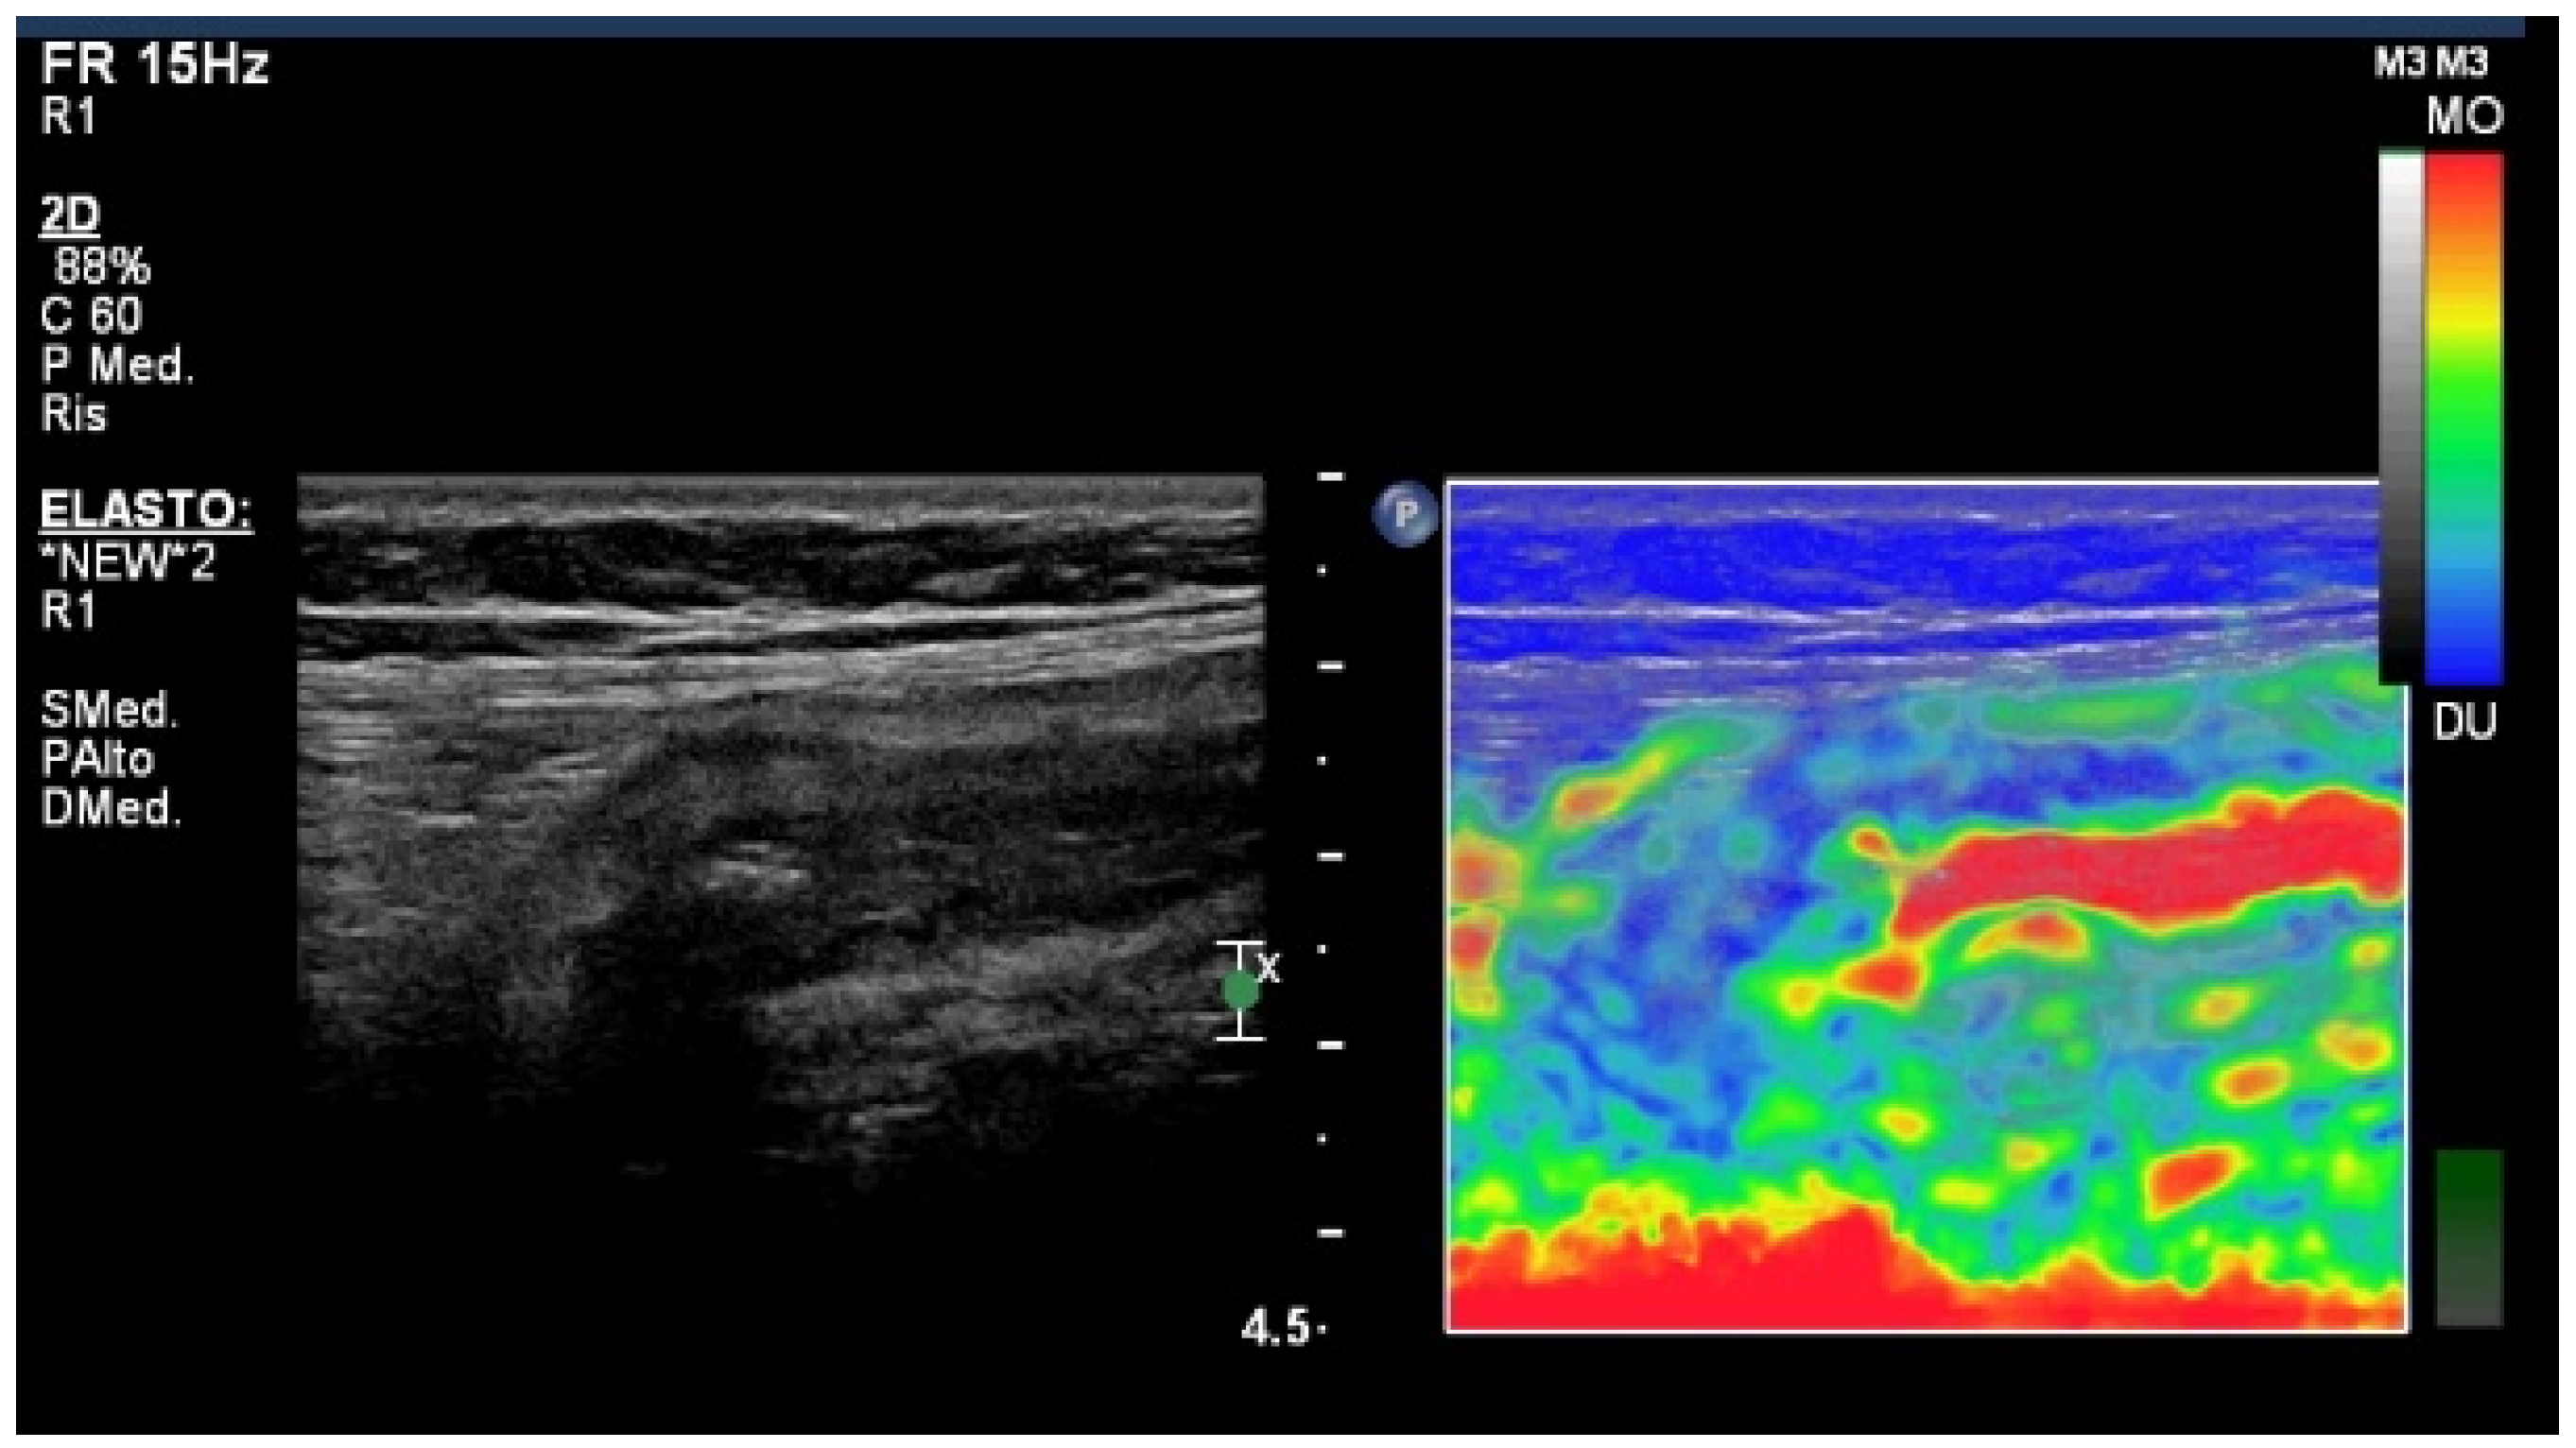

4. Elastography Imaging Techniques

- Fraquelli, M.; Branchi, F.; Cribiù, F.M.; Orlando, S.; Casazza, G.; Magarotto, A.; Massironi, S.; Botti, F.; Contessini-Avesani, E.; Conte, D.; et al. The Role of Ultrasound Elasticity Imaging in Predicting Ileal Fibrosis in Crohn’s Disease Patients. Inflamm. Bowel Dis. 2015, 21, 2605–2612. [Google Scholar] [CrossRef]

- Baumgart, D.C.; Müller, H.P.; Grittner, U.; Metzke, D.; Fischer, A.; Guckelberger, O.; Pascher, A.; Sack, I.; Vieth, M.; Rudolph, B. US-based Real-time Elastography for the Detection of Fibrotic Gut Tissue in Patients with Stricturing Crohn Disease. Radiology 2015, 275, 889–899. [Google Scholar] [CrossRef]

- Re, G.L.; Picone, D.; Vernuccio, F.; Scopelliti, L.; Di Piazza, A.; Tudisca, C.; Serraino, S.; Privitera, G.; Midiri, F.; Salerno, S.; et al. Comparison of US Strain Elastography and Entero-MRI to Typify the Mesenteric and Bowel Wall Changes during Crohn’s Disease: A Pilot Study. Biomed. Res. Int. 2017, 2017, 4257987. [Google Scholar] [CrossRef]

- Serra, C.; Rizzello, F.; Pratico’, C.; Felicani, C.; Fiorini, E.; Brugnera, R.; Mazzotta, E.; Giunchi, F.; Fiorentino, M.; D’errico, A.; et al. Real-time elastography for the detection of fibrotic and inflammatory tissue in patients with stricturing Crohn’s disease. J. Ultrasou. 2017, 20, 273–284. [Google Scholar] [CrossRef]

- Ding, S.; Fang, Y.; Wan, J.; Zhao, C.; Xiang, L.; Liu, H.; Pu, H.; Xu, G.; Zhang, K.; Xu, X.; et al. Usefulness of Strain Elastography, ARFI Imaging, and Point Shear Wave Elastography for the Assessment of Crohn Disease Strictures. J. Ultrasound Med. 2019, 38, 2861–2870. [Google Scholar] [CrossRef]

- Zhang, M.; Xiao, E.; Liu, M.; Mei, X.; Dai, Y. Retrospective Cohort Study of Shear-Wave Elastography and Computed Tomography Enterography in Crohn’s Disease. Diagnostics 2023, 13, 1980. [Google Scholar] [CrossRef]

- Chen, Y.; Mao, R.; Li, X.; Cao, Q.; Chen, Z.; Liu, B.; Chen, S.; Chen, B.; He, Y.; Zeng, Z.; et al. Real-Time Shear Wave Ultrasound Elastography Differentiates Fibrotic from Inflammatory Strictures in Patients with Crohn’s Disease. Inflamm. Bowel Dis. 2018, 24, 2183–2190. [Google Scholar] [CrossRef]

- Lu, C.; Gui, X.; Chen, W.; Fung, T.; Novak, K.; Wilson, S.R. Ultrasound Shear Wave Elastography and Contrast Enhancement: Effective Biomarkers in Crohn’s Disease Strictures. Inflamm. Bowel Dis. 2017, 23, 421–430. [Google Scholar] [CrossRef]